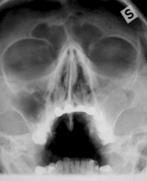

Perinteisenä NSO-rtg kuvauksena on ollut 1-3 kuvan sarja. Sarjaan on kuulunut suora etukuva (Caldwell-Luc), kuutamokuva (Waters) ja sivukuva. Lapsilta on tavallisesti tutkittu vain kuutamokuva. Perinteisen natiivikuvauksen ongelmana on huono osuvuus ja säderasitus. Säderasitus on liian iso jos kuvauksia on neljästi vuodessa. Tutkimuksen spesifisyys on korkea mutta sensitiivisyys matala.

Natiivikuvat: Suora etukuva (Caldwell-Luc), Kuutamokuva (Waters) ja sivukuva